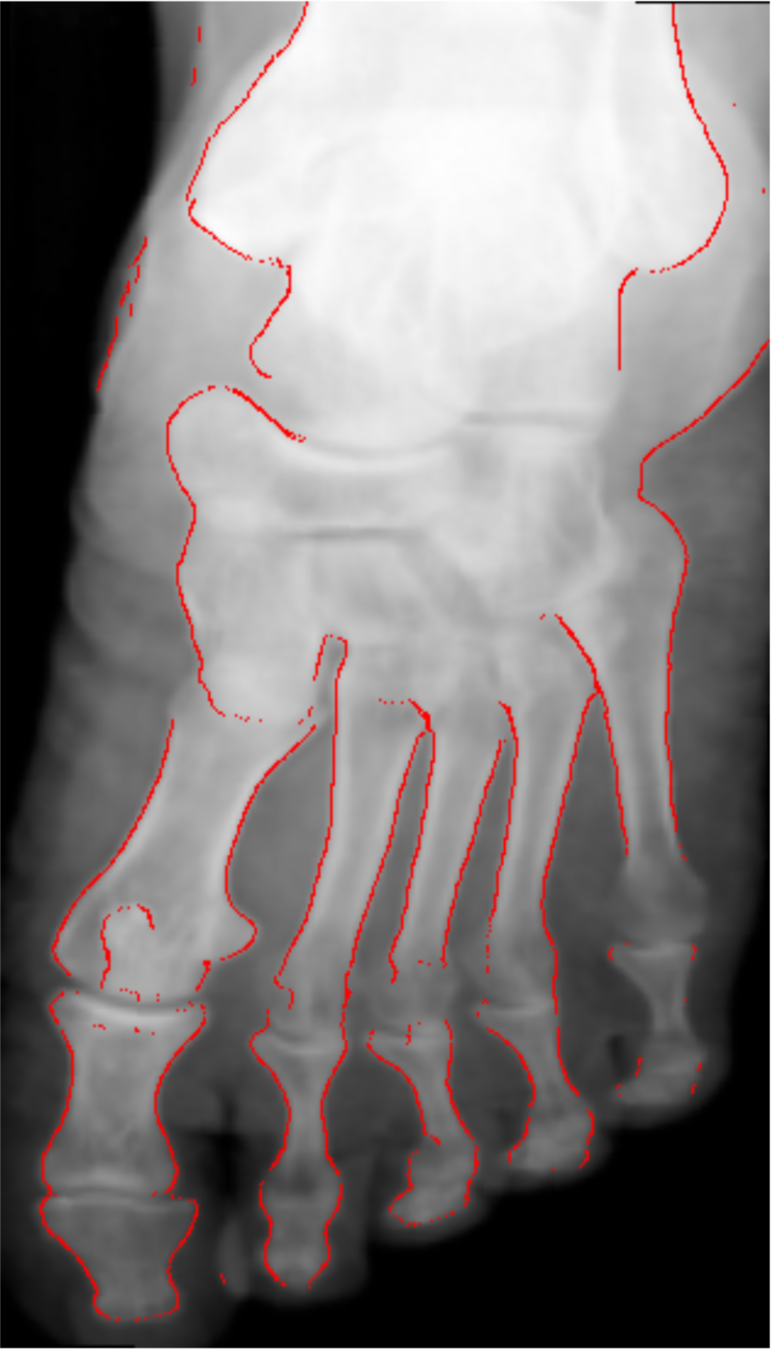

Detect bone and soft-tissue on X-Ray images

Detect

collimator

Segment

Open beam

Bone

Soft-tissue

Comparison with other methods

- Smooth connected boundaries.

- Better generalisation to different body parts (we do not have any frontal view of a foot in our dataset).

- More robust to noise.